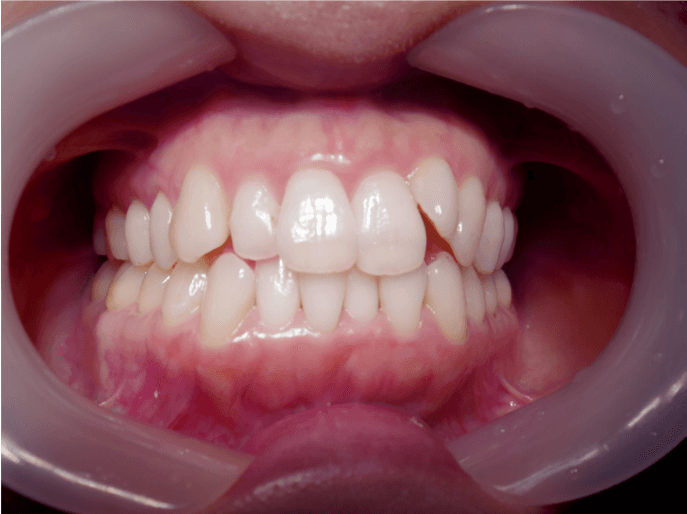

叢生(翼状捻転  Case3)

BEFORE

AFTER

担当医コメント

上顎前歯に捻転、上下顎に叢生が見られる。上顎臼歯の遠心移動、側方拡大、IPRを用いて歯列の改善をインビザライン治療で行う事にした。

また上顎中切歯の形態に左右差があり、切縁の形態に特徴があるため、削合による形態修正を行う事とした。

患者は協力度が高く装置を20時間以上きちんと使えており、治療が順調に経過したため、装置の交換ペースを1週間ではなく5日間で治療をすすめた。

治療の概要

年齢/性別

20代 女性

主訴

前歯が気になる。上下の歯並びが気になる。

リスク

歯肉退縮が起こる可能性がある。

費用

85万円(矯正費用)

期間

1 6 ヶ月